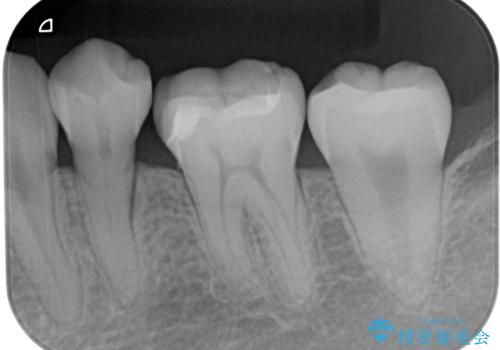

- 他院で保険の詰め物を行い、割れたためやり替えたいとのことで来院された患者様です。

セラミックの詰め物(セラミックインレー)とセラミックにプラスチックを混ぜた詰め物(ハイブリッドインレー)の二種類のメリット、デメリットを説明したうえで、患者様のご希望でハイブリッドインレーで治療をしていくことになりました。

拡大鏡視野下で、保険の詰め物、虫歯の除去を行い、ハイブリッドインレーに適した形に整えました。